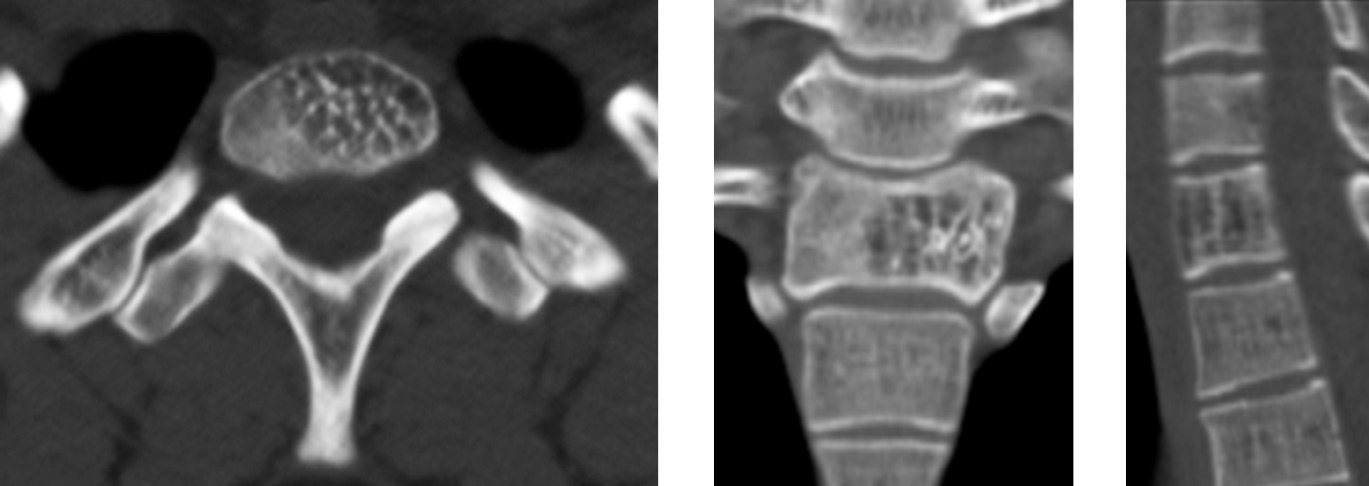

Clinical case 2. Patient V., 17 years old, presented to the institute in May 2018, due to complaints of pain in the cervical and thoracic spine with irradiation to the right upper limb. The pains were dragging and periodic, aggravated by physical exertion. The patient estimated her pain at 6 points as per the VAS. On palpation of the spinous processes of the С7–Th1 vertebrae, an increase in pain syndrome was noted. CT examination showed an aggressive hemangioma of the Th1 vertebral body (Fig. 3). In addition to the clinical symptoms, the aggressiveness of hemangioma was characterized by the CT signs, such as bone expansion with protrusion of the cortical layer; a lesion larger than 2/3 of the vertebral body; damage (thinning) of the cortical layer; and uneven trabecular structure of the hemangioma.

Fig. 3. CT scans of the vertebra Th1 of patient V. before the surgery